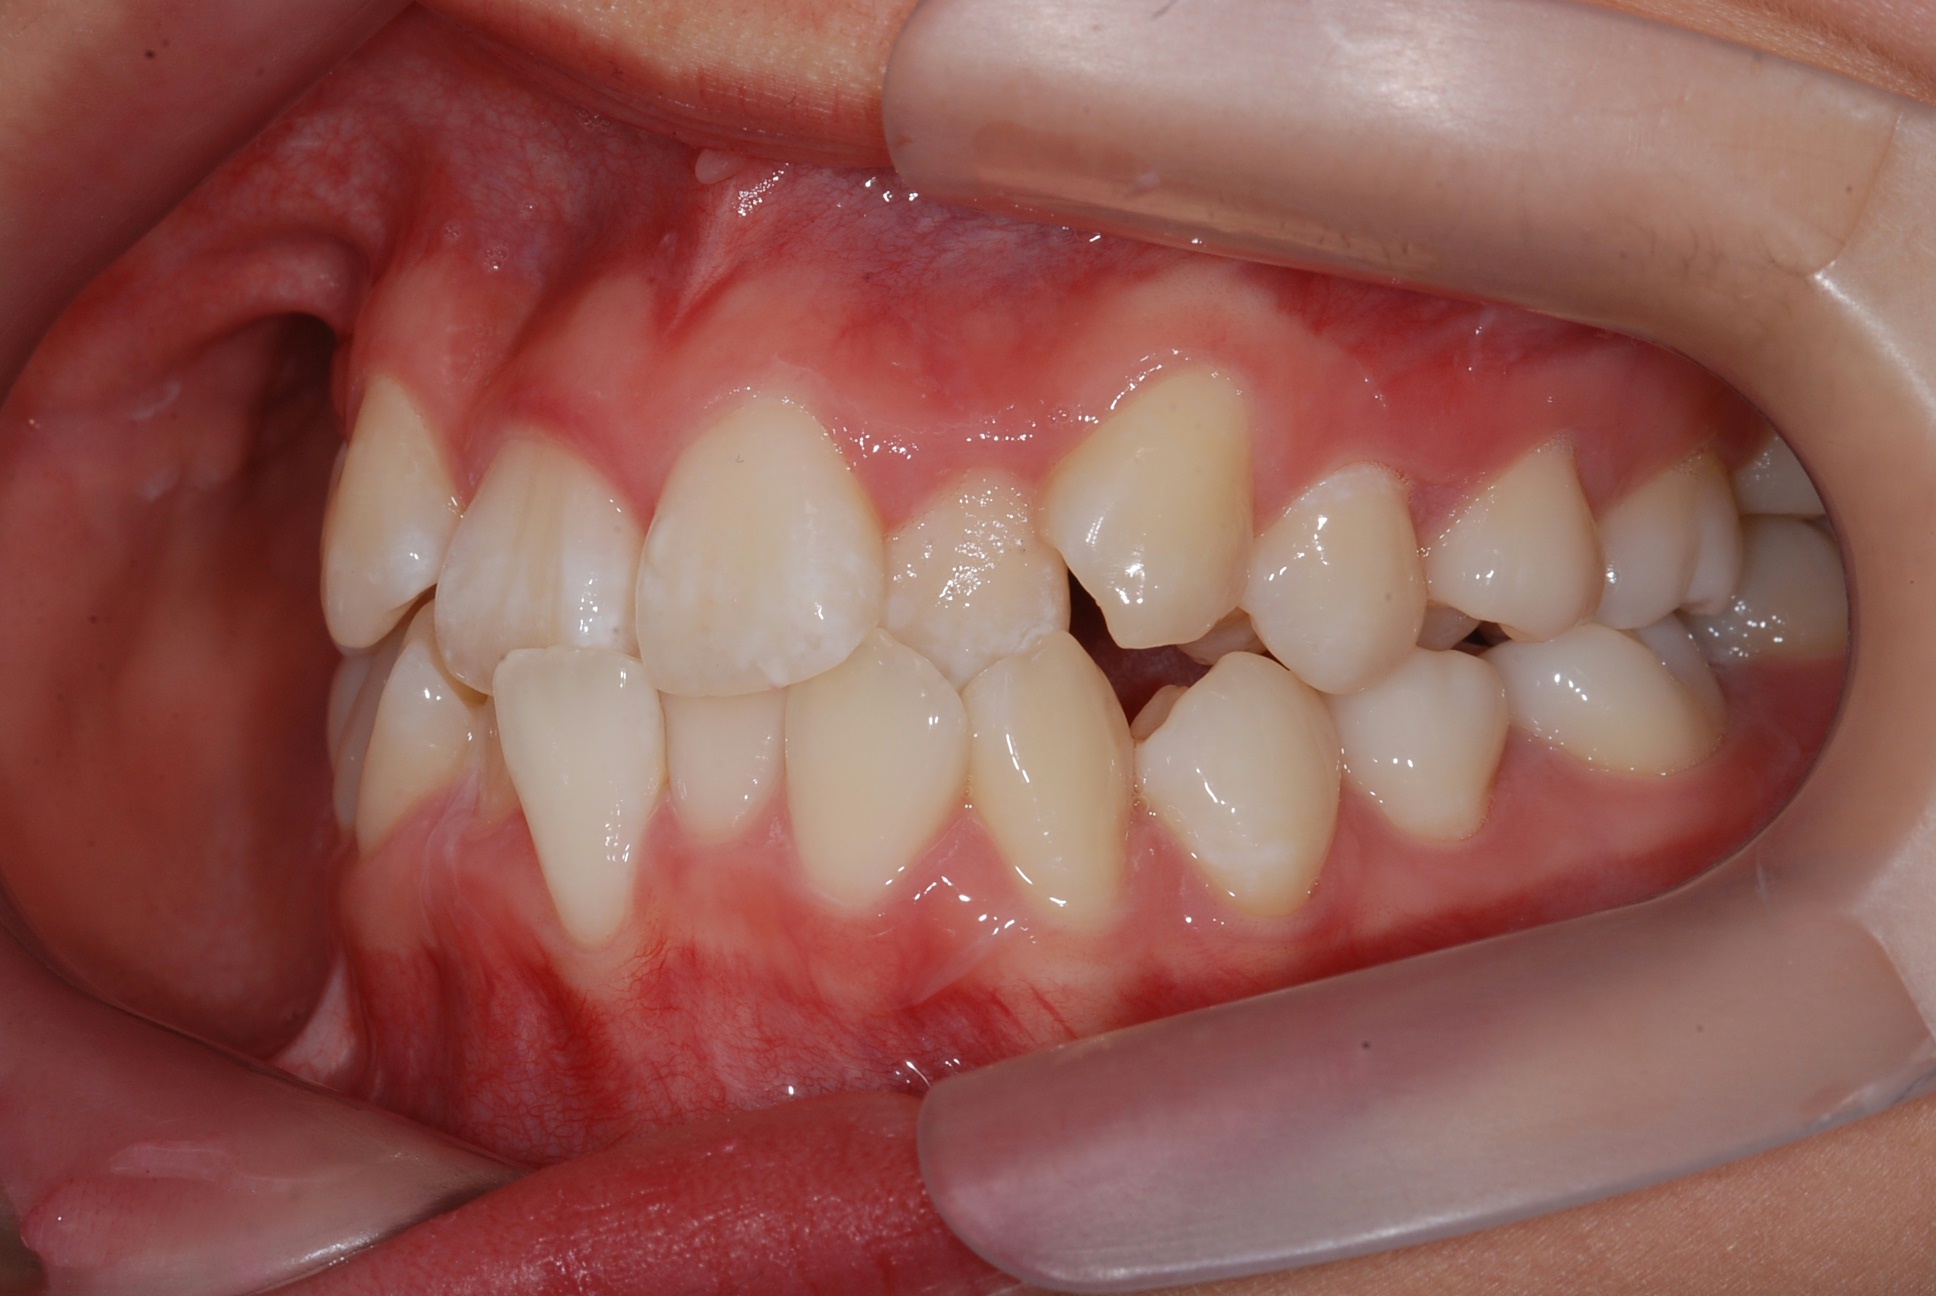

치료 전 사진입니다.